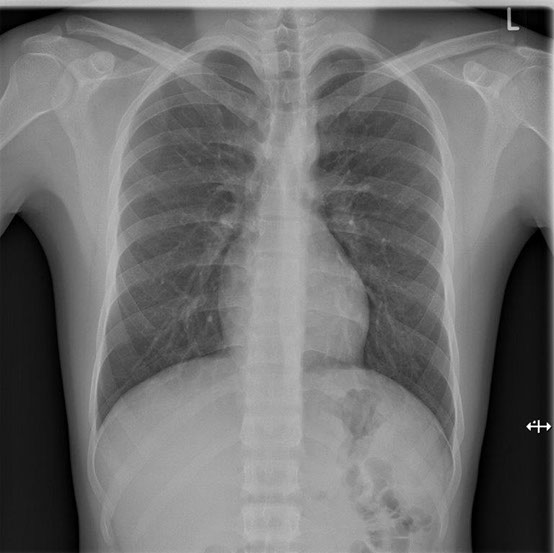

Herz-/Lungenröntgen (Thorax-Röntgen)

Diese Untersuchungen werden zum Beispiel zur Beantwortung folgender Fragestellungen / bei folgenden Beschwerden eingesetzt:

Untersuchungsablauf:

Die Untersuchung muss mit tiefer Einatmung (Inspiration) durchgeführt werden. Dies erlaubt eine bessere Beurteilbarkeit der Lunge. Es ist auch wichtig, dass Sie sich während der Aufnahme nicht bewegen. Es werden zwei Aufnahmen im Stehen gemacht. Im Anschluss an das Röntgen wird von der Radiotechnologin die Bildqualität geprüft und erfolgt danach die Befundung durch den Radiologen.